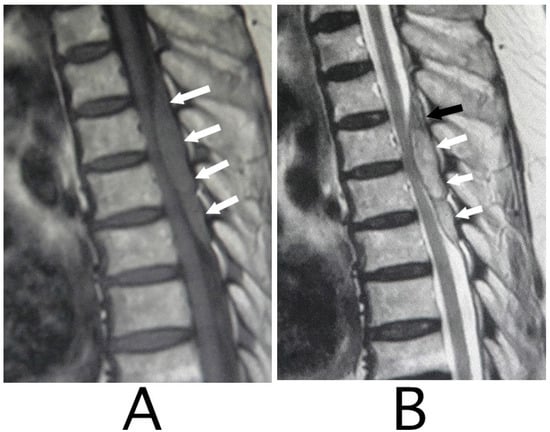

MRI of the spinal cord analysis was performed because the presence of acute lesions on the spinal cord was suspected, based on neurological findings and the clinical course. As a result, sagittal T1-weighted MRI showed an iso-intensity mass in the epidural space behind the spinal cord at the level from Th3 to Th6 (Figure 1A). Compression of the spinal cord was shown at the level between Th4 and Th6 (Figure 1A,B). The lesion was delineated as a high-intensity mass with heterogeneity and a superiorly adhered iso-intensity region in sagittal T1-weighted images (Figure 1B). Axial T1-weighted MRI showed an iso-intensity mass in the posterior part of the epidural space and a deviation of the spinal cord to the anterior direction (Figure 2A). The lesion was delineated as a heterogeneous high-intensity mass in axial T2-weighted MRI images (Figure 2B).

Figure 2. Axial MRI. An iso-intensity mass was identified in the posterior part in the epidural space (white arrows) (T1-weighted image; (A)). The lesion was delineated as a heterogeneous high-intensity mass (white arrows) (T2-weighted image; (B)). The spinal cord was compressed in the anterior direction (black arrows) (A,B). (Rt = right).